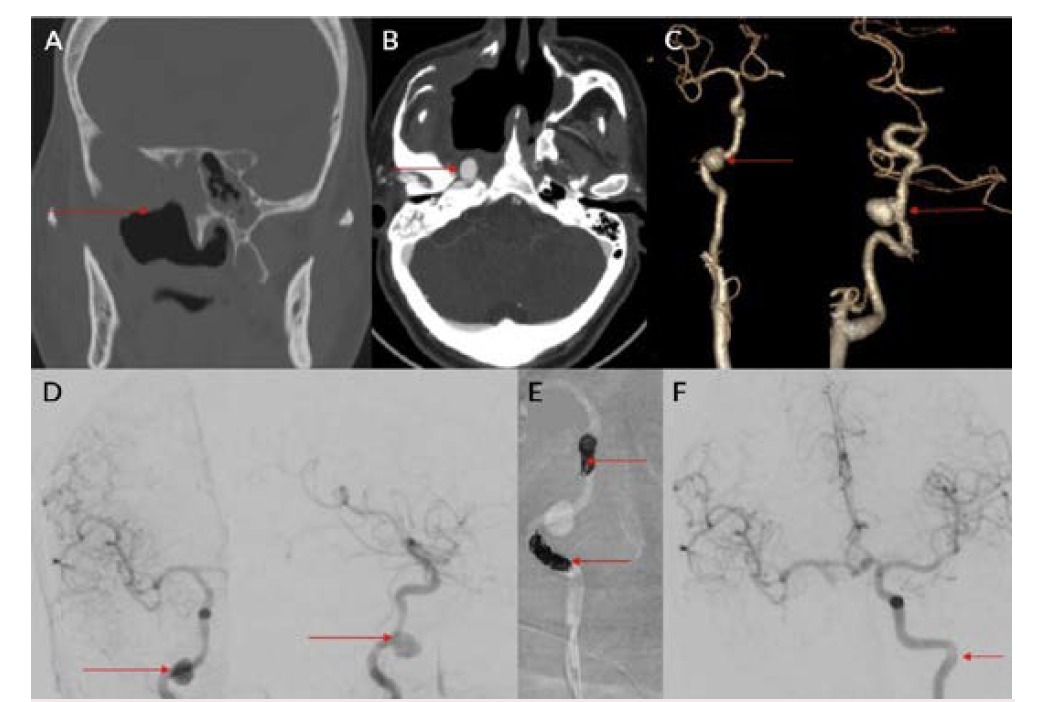

COVID-19 infection has affected people worldwide since 2020 after its initial outbreak in Wuhan, China. It has caused significant mortality and morbidity, causing millions of deaths to date. COVID-19 infection is known to affect multiple organs such as the lungs, heart, brain, and skin, with the lung being most common.1 Patients with COVID-19 usually present with complaints of fever, cough, malaise, and difficulty breathing.1 Diabetes mellitus is an independent risk factor for COVID-19 infection.1 Fungal infection was a known complication following COVID-19 infection, especially in those with poorly controlled blood sugar and who have been treated with immunosuppressive agents such as steroids.2,3 Pulmonary complications following COVID-19 infection were mainly related to fibro-cavitary changes.3-5 Hemorrhage following fungal infection was mainly due to vascular involvement and formation of pseudoaneurysm.6 Patients with severe COVID-19 infection may have endothelial inflammation and secondary fungal infection, leading to pseudoaneurysm formation with a risk of increased bleeding.5,6 Fungal sinusitis following COVID-19 infection is a well-known entity that can cause bleeding due to the involvement of the internal and external carotid vessels.2,3,5 Extracranial carotid artery aneurysms are found most frequently in the common carotid artery at or near the bifurcation, less frequently in the internal carotid artery (Figures 7A and 7B), and least often in the external carotid artery.7,8 Ongoing studies of the precise molecular underpinnings of mycotic pseudoaneurysms suggest that arterial wall breakdown is likely caused by matrix-degrading enzymes produced by either seeded bacteria or inflammatory cells of the host response.6 Diabetes and fungal infections are more frequently documented, which could result in mycotic aneurysm, spontaneous rupture, and massive hemorrhage.2,3,5

Pulmonary artery pseudoaneurysm is a rare but important entity because of its high risk of life-threatening hemorrhage.2,5,9,10 Peripheral branches of the lower lobe pulmonary artery are most commonly affected.2,5,10 A pseudoaneurysm is different from a true aneurysm because there is no wall except for the hematoma that is surrounding and containing it.6,9,11,12 The etiology of a pulmonary artery pseudoaneurysm is inflammatory erosion secondary to tuberculosis (Rasmussen aneurysm), necrotizing pneumonia, bacterial endocarditis, mucormycosis, or vasculitides (Marfan syndrome, Behçet’s disease, etc.). Other causes include necrotic cavitary lung carcinoma, congenital heart disease, and traumatic injury. Iatrogenic pseudoaneurysm secondary to pulmonary artery catheter placement has also been reported.4-6,9-11 Internal maxillary artery pseudoaneurysm is rare and is more commonly encountered following trauma and iatrogenic injury (Figures 8A and 8B).7,8,13 These patients present with massive or moderate bleeds, which can lead to death in about 50% of cases if left untreated.2,4 The most common artery leading to hemoptysis is the bronchial artery, which constitutes around 80% to 90%.4,5,13 Hemoptysis related to the pulmonary artery constitutes around 10%.10,14 Multidetector computed tomography (MDCT) pulmonary angiography is the modality of choice to diagnose pulmonary artery aneurysms.2,9,10,12 It provides detailed information about the presence, number, size, shape, and origin of pulmonary artery aneurysms.2,9,10 MDCT also allows detailed assessment of the orientation and size of the aneurysmal sac and size of the neck on multiplanar reconstruction.2,10 It also gives an overall idea about the pathology, and the involved lung segment eventually helps in planning the treatment accordingly.4,10,12,14 Digital subtraction angiography has the advantage of allowing endovascular intervention at the time of diagnosis.4,12,14 Ultrasound and magnetic resonance imaging are also used in cases of aneurysms involving neck vasculature.2,14,12